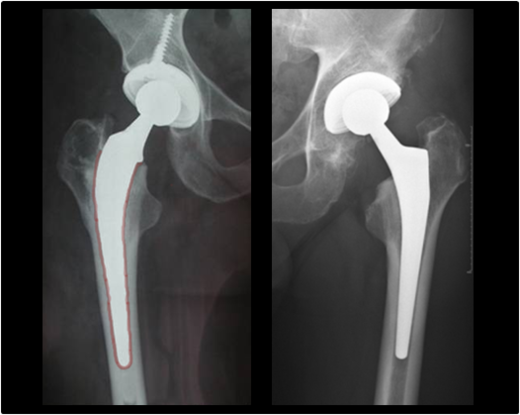

Bei jüngeren Patienten kommt es insbesondere auf den Erhalt von Knochensubstanz an. Mit diesem Ziel sind sogenannte Kurzschäfte entwickelt worden (s. Röntgenbild). Die von uns verwendeten Kurzschäfte erhalten an hüftnahen Oberschenkelknochen insbesondere einen Teil des Schenkelhalses und verankern sich teilweise auch in diesem.

Links: Zementiert (rot markiert) Rechts: Zementfrei